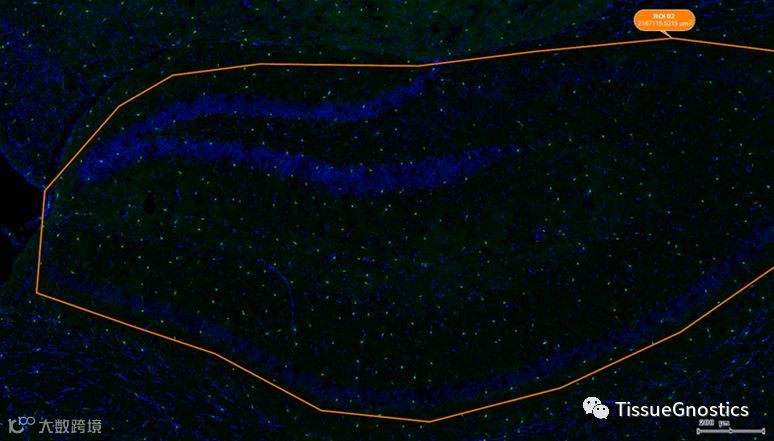

神经退行性疾病,又称神经退化障碍(Neurodegenerative Disease),是一类以大脑和脊髓的细胞神经元逐渐退化死亡所直接导致的疾病,影响人类的运动感知与记忆认知相关功能。由于啮齿类实验动物模型并不足以完全模拟人类神经退行性疾病的病理生理机制,借助灵长类实验动物进行大尺寸样本的全景分析就成为一种必然的选择。TissueFAXS Cytometry 具有的超大尺寸玻片高倍油镜全景获取技术,可以保留超大脑片中光学极限分辨率下的所有细节,构建虚拟玻片,并对其微小的结构,如 Aβ斑块,进行不同脑区的数字化分析,获得准确客观的量化数据。